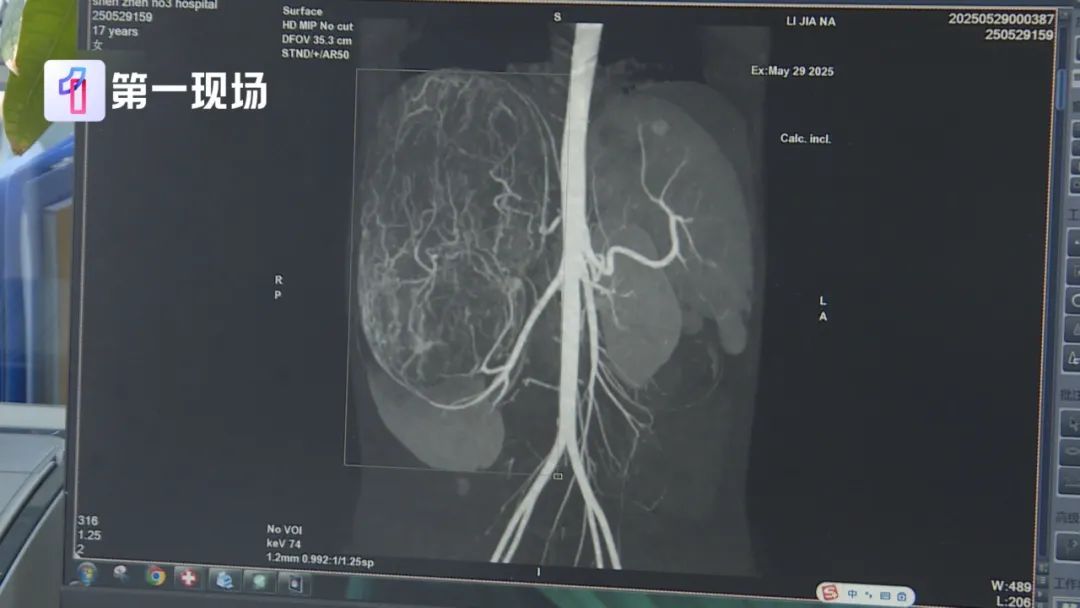

等到了当地医院一检查,CT结果显示,她的右肾有恶性肿瘤伴肝转移可能,家长就立即带着孩子来到深圳求医。